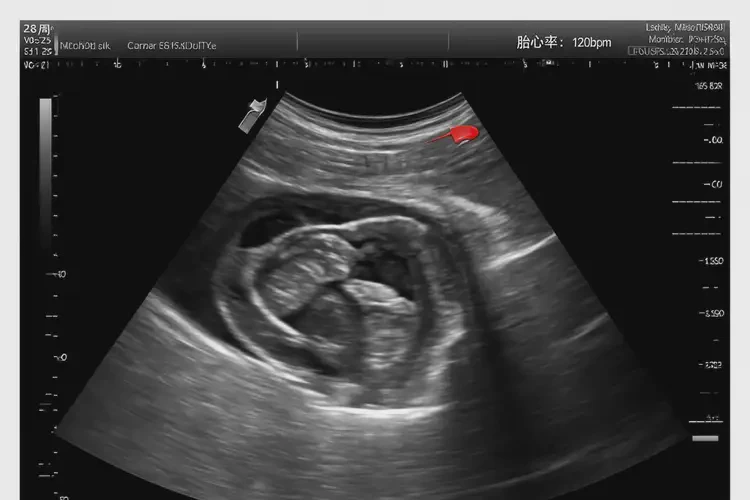

孕28周胎心113正常嗎(圖1)

孕28周胎心113正常嗎(圖2)

孕28周胎心113正常嗎(圖3)

孕28周胎心113正常嗎(圖4)